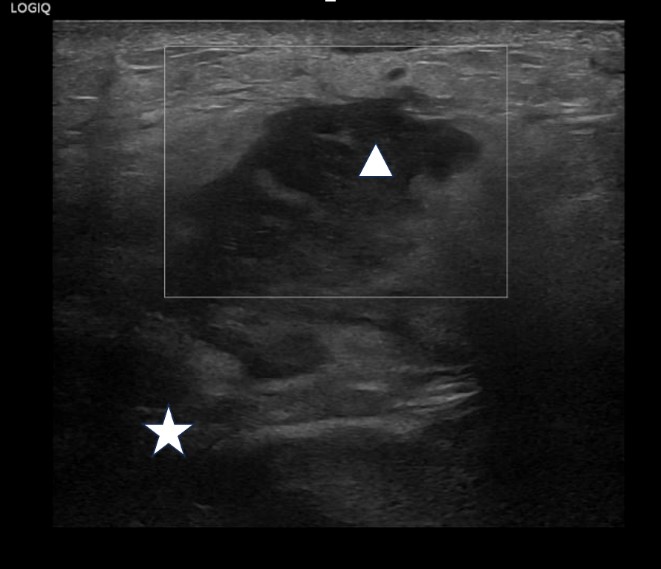

B-mode ultrasound demonstrated gross left sided hydronephrosis with thinning of the renal cortex which is in keeping with previous imaging (fig1). However, deep to the clinically obvious swelling on the left flank there was an irregular heterogeneous fluid collection which extended from the superficial soft tissues/skin to the lower pole region of the left kidney with which it appeared intimately associated (fig2, fig3 and Fig 4). These findings were concerning for a large renal abscess which may have progressed to a perirenal abscess and developed a sinus tract extending to the skin surface. In light of the elevated CRP, urgent cross-sectional imaging and urgent clinical review by the urology team was conducted. The right kidney and urinary bladder were unremarkable on ultrasound.

| Figure 2: Lower pole of the left kidney with the abscess seen extending into the extrarenal space (Star: Lower pole of the left kidney, Circle: Sinus tract) |